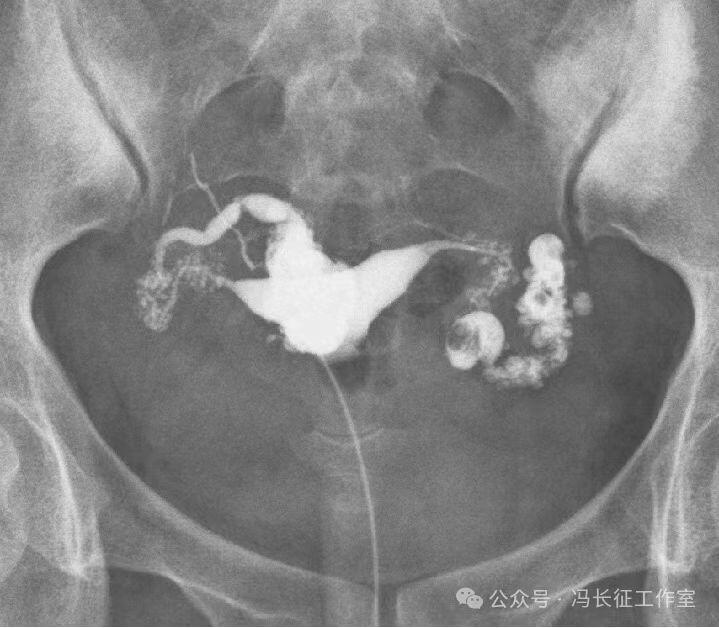

输卵管积水的子宫输卵管造影尽量包括这5个方面的描述,诊断的临床意义才最大,这样才能给好的生殖科医生有价值的建议,帮助给不孕者制定最好的助孕治疗方案。比如这例输卵管积水,峡部结节性输卵管炎(病因),交通性(积水近端是否和宫腔相通),中度(积水大小),厚壁(管壁的厚度),多囊(囊腔的多少)。

微信图片_20240220111109(1).jpg

最后诊断应该是:双侧峡部结节性输卵管炎并双侧中度、厚壁、多囊、交通性输卵管积水。